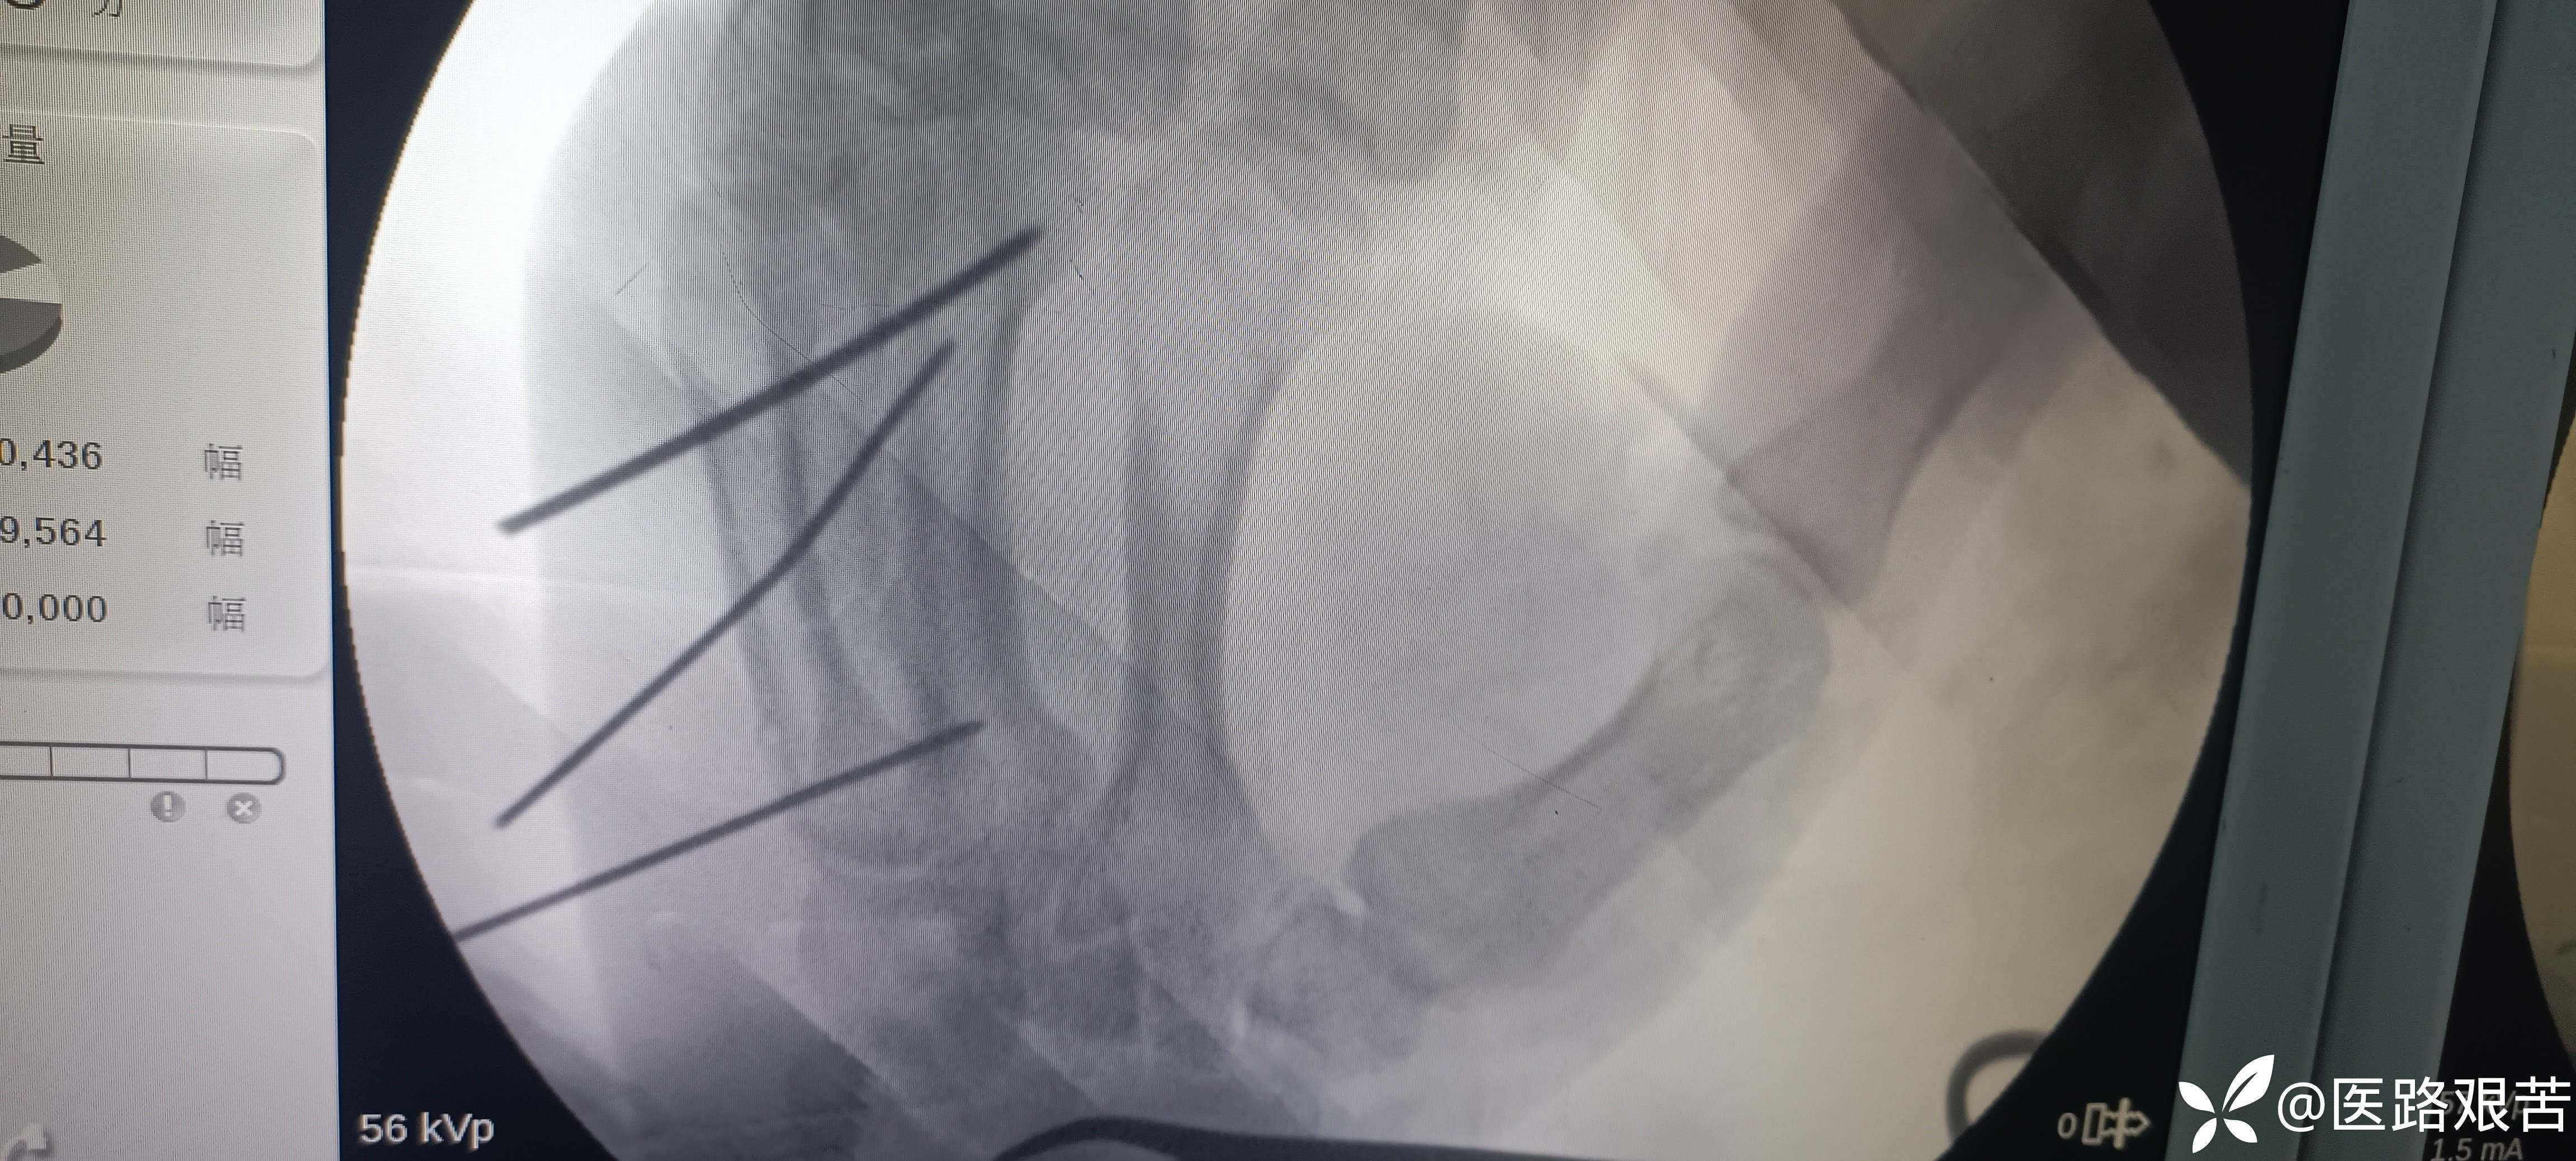

患者,男,32岁,外伤摔倒致右手第四掌骨骨折,伤后1天就医,手法复位石膏固定后,表示骨折立线正,可接受,愈合时间稍长,患者要求解剖复位,并希望早日活动。

受伤后DR